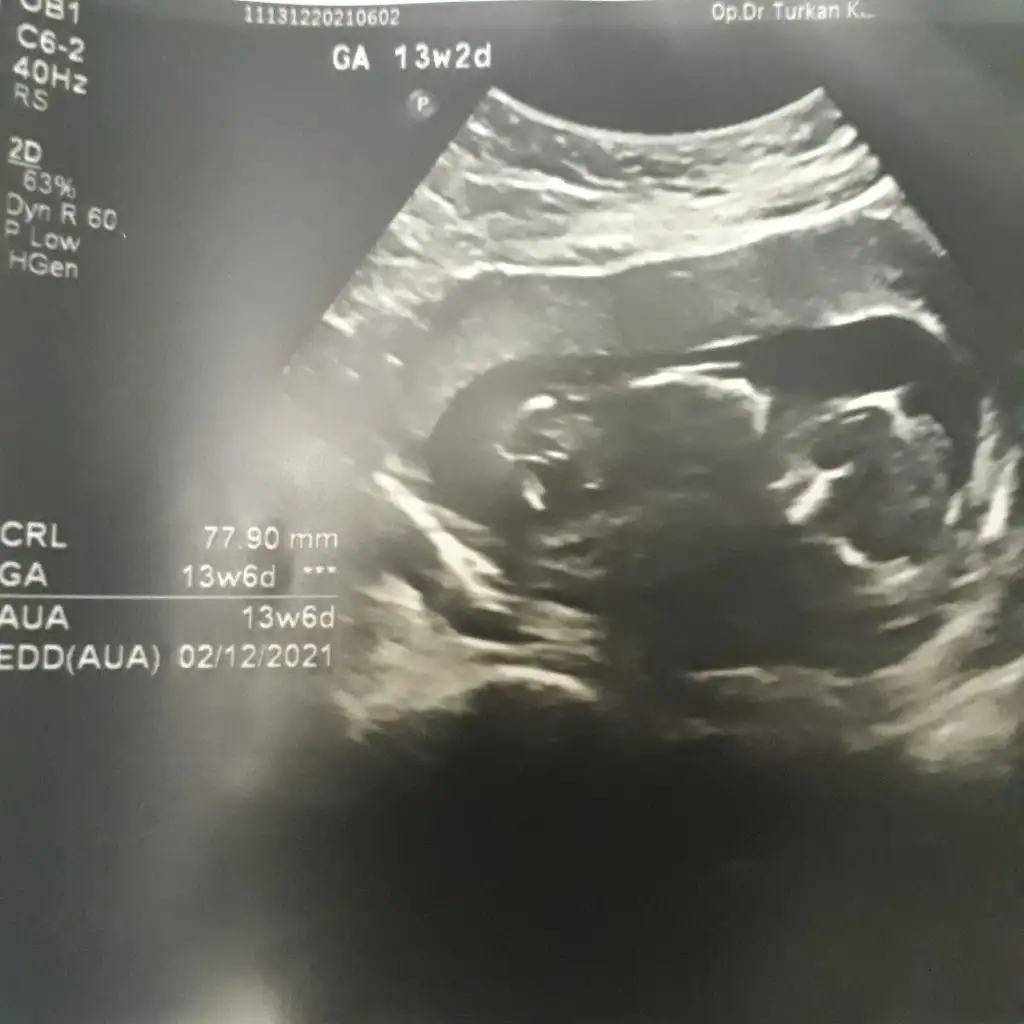

Bende yeniyim öncelikle☺️Mesajlarınızı dikkatle okudum bana da doktorum kesin birşey demedi 13.haftadayım yorumlar Mısınız acaba

dr soylemeden siz gorun genital nub teorisi ( bebegin cinsiyeti)

Nuba göre kız mı erkek mi sizce kızlar?